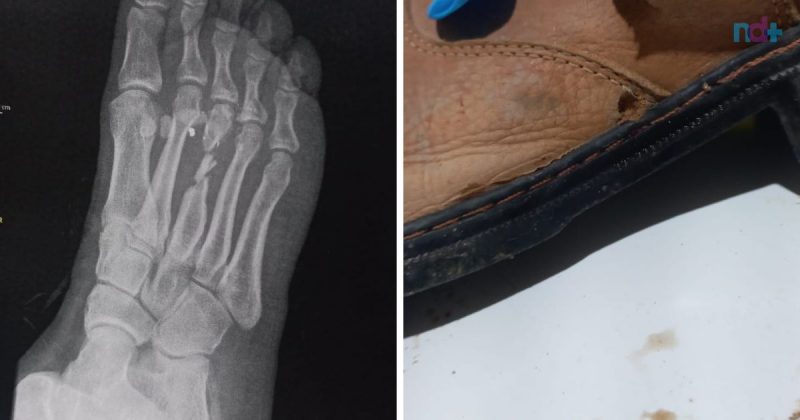

Tiro no pé foi disparado por vizinho de terreno em TijucasVítima foi questionar vizinho ao comprar terreno de 16 hectares e perceber que haviam apenas oito, mas acabou levando tiro no pé, literalmente – Foto: Polícia Militar/Reprodução

Mesmo com a vítima tentando fugir, o homem atirou e a bala atingiu de baixo do pé direito e saiu na parte de cima do pé. Em imagens compartilhadas pela Polícia Militar, é possível ver os furos nos calçados. O suspeito dos disparos ainda não foi identificado.